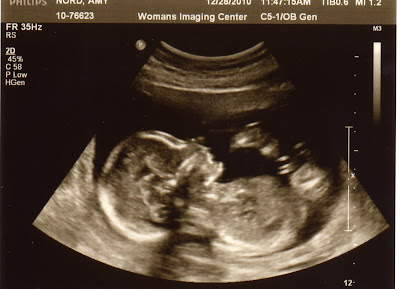

Ultrasound Pics at 18 weeks in the words of baby....

Dec- What a busy month getting ready for Christmas. We had so much to celebrate this month. On the 28th we found out we were having a little boy and on the 30th we celebrated 15 wonderful years of marriage! What an amazing month! We also found out I have placenta previa but that our little boy is perfectly healthy, it just means mommy has to take it very easy for a while.